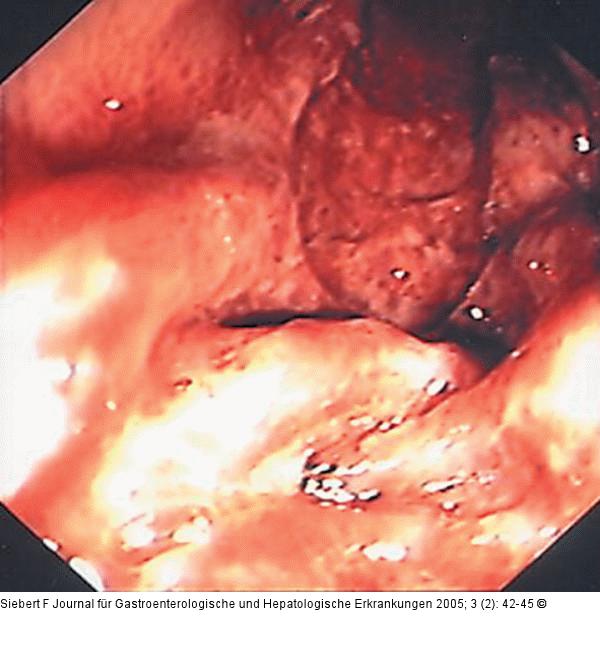

Abbildung 9a-d: Kolon-Ischämie - Differentialdiagnosen Differentialdiagnose Ischämische Colitis (oben) – Pseudomembranöse Colitis (unten) |

Abbildung 9a

Abbildung 9a-d: Kolon-Ischämie - Differentialdiagnosen

Differentialdiagnose Ischämische Colitis (oben) – Pseudomembranöse Colitis (unten) |